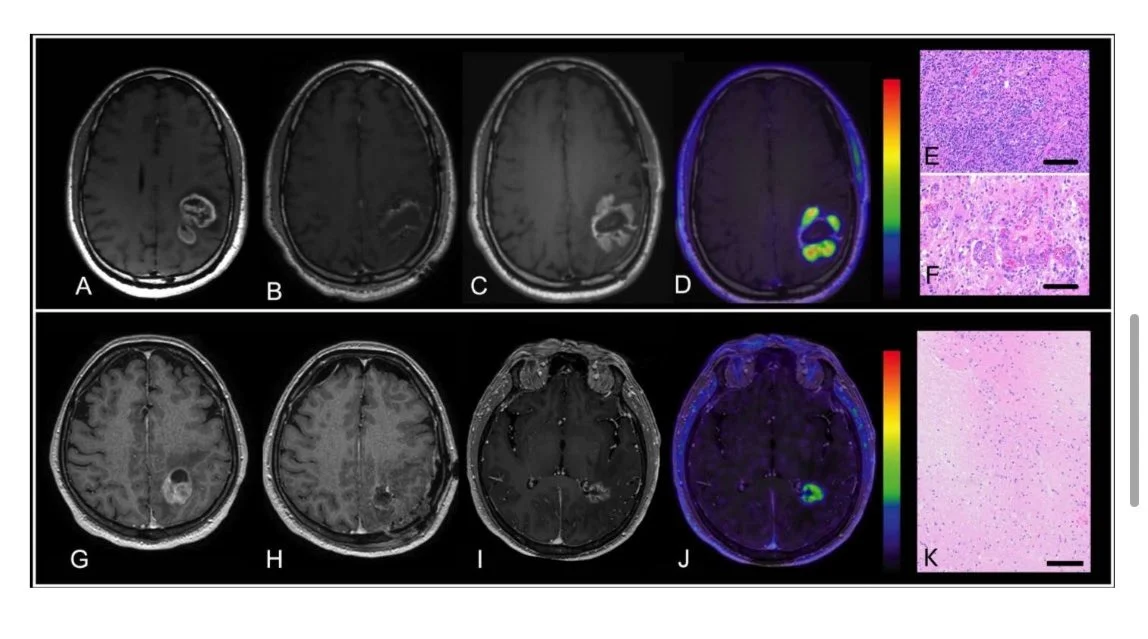

Title: Clinical Utility of [F18]-Fluciclovine PET/MRI for Differentiating True Progression from Treatment-Related Changes in Patients with Glioblastoma

Evaluating retrospectively a multi institutional, clinical real-world cohort of patients with GBM in the post chemo-RT setting, we found excellent diagnostic accuracy of fluciclovine in differentiating PD from treatment related change.

One of the most challenging aspects of glioblastoma is post radiochemotherapy evaluation – is it tumor progression? Or RT sequela?